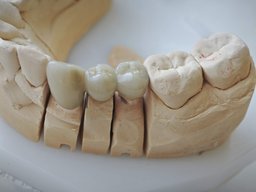

Das Sägemodell

Der Zahntechniker stellt nach der Abformung zunächst ein Sägemodell her, auf dem Implantat-Abutment und Zahnstumpf einzeln herausnehmbar sind. Die Unteransicht zeigt den Unterschied zwischen den beiden Pfeilern deutlich: links der konisch zulaufende Zahnstumpf, rechts der zylindrische Hohlraum des Implantat-Abutments.

Die fertige Brücke auf dem Modell

Die fertige dreigliedrige Metallkeramikbrücke sitzt auf dem Sägemodell.